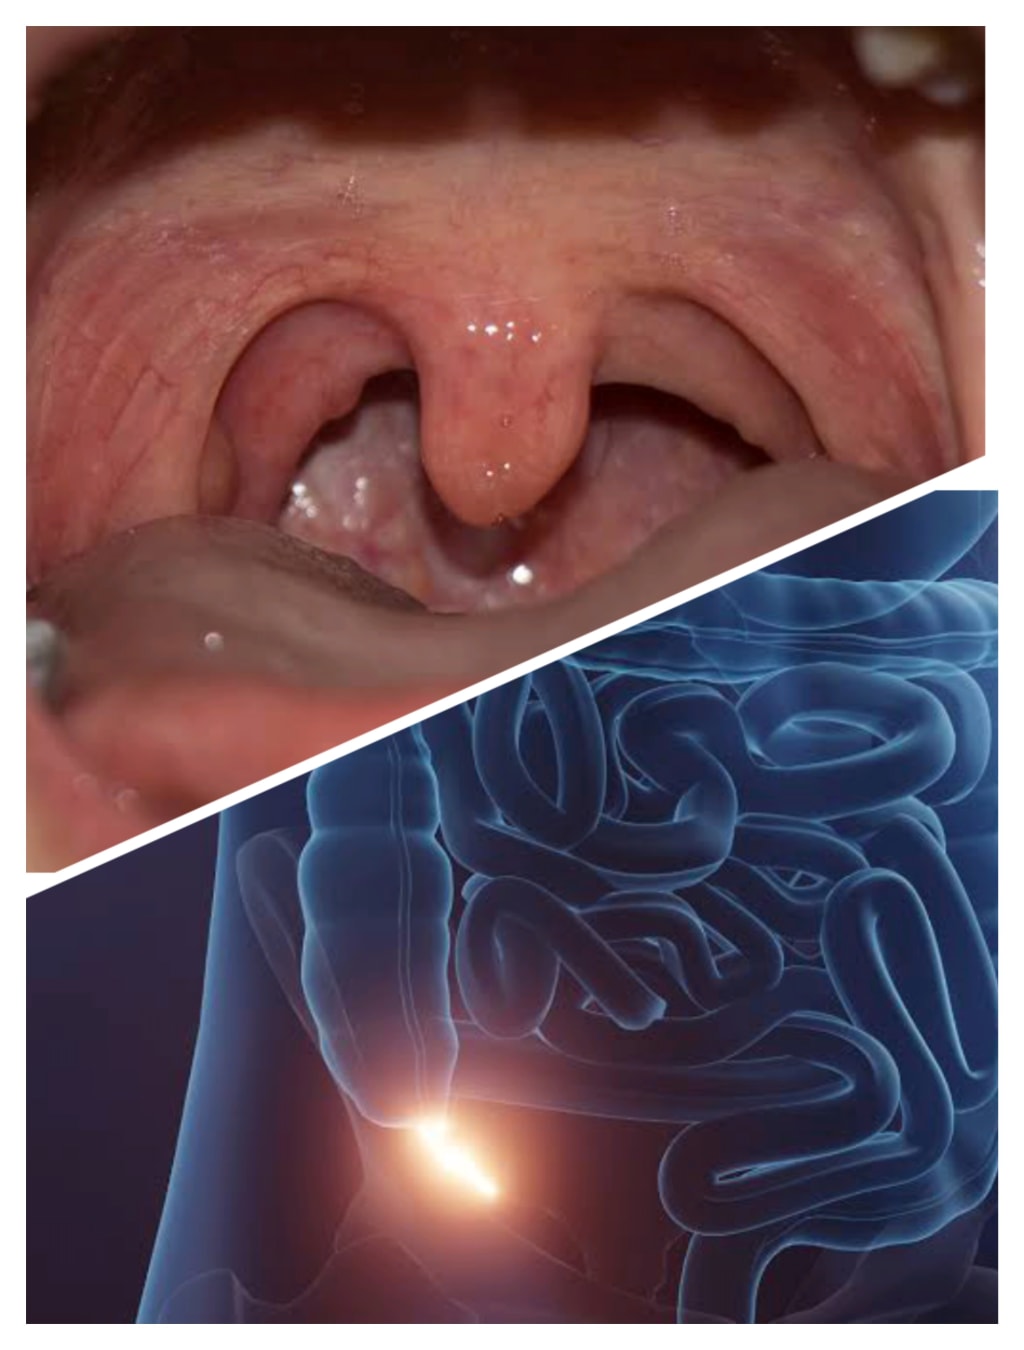

What is Uvula?

Uvula is a soft, flexible muscle which is hinged inside the oral cavity of humans. The scientific name of uvula is palatine uvula. The uvula is made up of connective tissues and small muscle fibers. The uvula also contains salivary glands that secret saliva.

As we know that, the oral cavity and nasal cavities are separated by a wall called the palate. The palate is divided into two parts; soft palate and hard palate. The hard palate is the front part of the palate which is bony that separate the nasal cavity from the oral cavity, and the soft palate is the back part of the palate, which lacks bone. The uvula is the end part of the soft palate which is hinged inside the mouth. Scientist have not found all the functions performed by Uvula. Before it was considered as a vestigial structure with no functions, but with the passage of time due to advance technology, scientists have found that uvula performs different important functions in our body.

What is Appendix?

The operation of appendix is a common term which we hear in our society. But what the appendix is? The Appendix is a finger like projection which is present in our abdomen and is connected with the colon. The colon is a pouch like structure present between the junction of small and large intestine. The appendix is also called vermiform, because it is worm like in shape.

Now, the researcher have found that the appendix has an important purpose in our body. The average length of appendix is 9 cm, but it can vary between 5 to 35 cm. The normal diameter of appendix is 6mm. If the diameter of appendix is more than 6 mm then that type of appendix is called inflamed appendix.